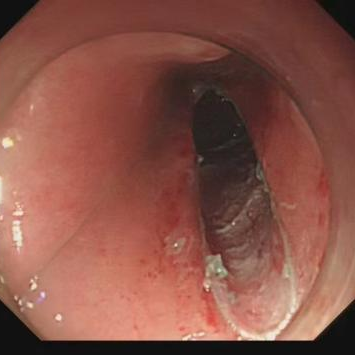

杨叶医生解释,经黏膜下隧道内镜肿瘤切除术(STER 术)就像在地铁隧道中施工:先在距离病灶上方 3 cm 的黏膜处开一个 2 cm 的「入口」,然后在黏膜下层建立「隧道」,进入隧道内,找到病灶并一点点沿病灶周围剥离后取出病灶,最后封闭隧道口。这样既能完整切除病灶,又最大限度保留食管黏膜完整性,大幅降低穿孔和感染风险。

手术当天,在消化内科、内镜中心、麻醉医师和胸外科团队的共同努力下,最终通过微创治疗的方式为付先生完整切除了这颗大小约 3.5*5 cm 的「土豆」。术后第 5 天,付先生便顺利出院了。